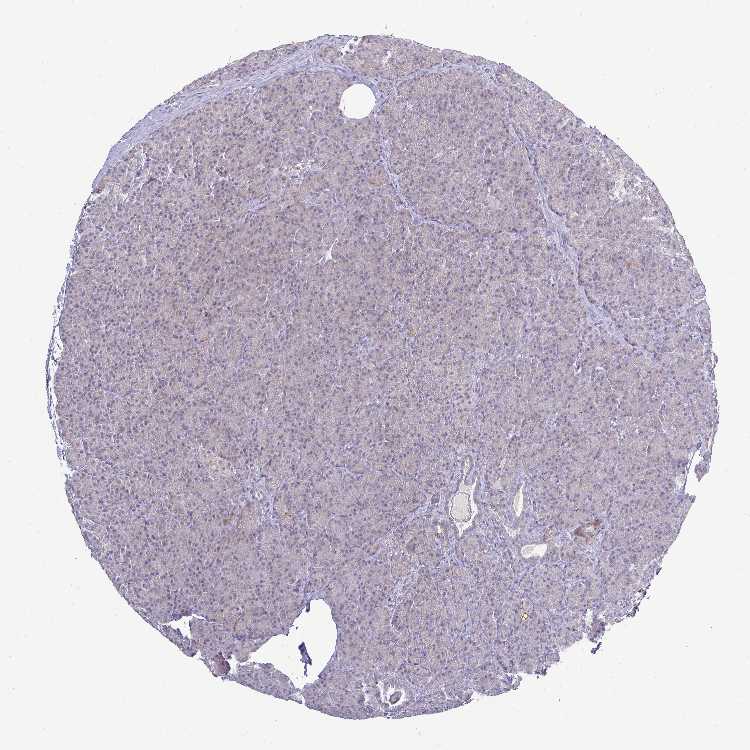

PANCREAS - Antibody stainingi

Antibody staining in the annotated cell types in the current human tissue is reported as not detected, low, medium, or high, based on conventional immunohistochemistry profiling in selected tissues. This score is based on the combination of the staining intensity and fraction of stained cells.

Each image is clickable and will lead to virtual microscopy that enables deeper exploration of all samples and also displays staining intensity scores, fraction scores and subcellular localization as well as patient and tissue information for each sample.

Antibody HPA001383Antibody CAB000043Antibody CAB020416Antibody CAB062555

Exocrine glandular cells MediumNot detectedNot detectedNot detected

Pancreatic endocrine cells LowNot detectedNot detectedNot detected